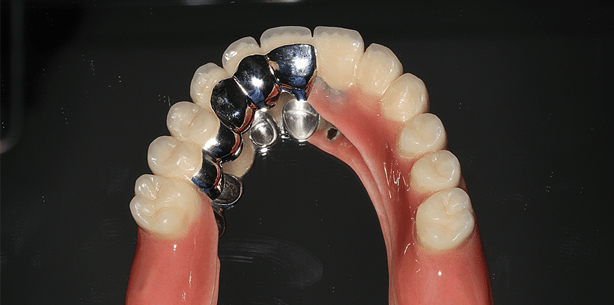

Dem Patienten wurden verschiedene ­Therapieoptionen aufgezeigt und auf die jeweiligen Vor- und Nachteile eingegangen. Nach intensiver Beratung entschlossen wir uns auch im Hinblick auf die Erweiterbarkeit und unter Berücksichtigung monetärer Erwägung für eine Teleskopversorgung auf NEM-Basis. Als natürlicher Pfeilerzahn wurde Zahn 15, 14, 12, 11 im Oberkiefer sowie Zahn 33, 43, 44 primärüberkront. Um eine lineare Abstützung und die damit einherge­henden, prognostisch ungünstigen Kippbewegungen zu vermeiden, sollte durch die Insertion von Implantaten Regio 23 und 24 ein ausgeglichenes Abstützungspolygon geschaffen werden. Nach der Extraktion der nicht erhaltungswürdigen Zähne und der druchgeführten Parodontaltherapie erfolgte eine Abheilphase von zehn Wochen. Es zeigte sich im Bereich des posterioren Alveolarkamms eine ausgeprägte Oberkieferatrophie mit unzureichendem vertikalen Knochenangebot beidseits. Um eine Sinusbodenelevation mit anschließender Augmentation zu vermeiden, wurde im Rahmen der Planung mittels 3-D-Diagnostik (digitale Volumentomografie) die Insertion von Kurzimplantaten in Erwägung gezogen. Die metrisch-präoperative Analyse mittels digitaler Volumentomografie (GALILEOS Comfort, Sirona Dental) ergab ein vertikales ­Knochenangebot von 9,7 mm Regio 23 und 6,2 mm Regio 24. Die transversale Messung der krestalen Kieferkammbreite betrug 6,6 mm Regio 23, respektive 6,4 mm Regio 24. Bedingt durch das eingeschränkte Knochenangebot wurde auf längenreduzierte Implantate (4,5 x 8 mm, Bicon Dental Implants) zurückgegriffen. Die Verwendung von Implantaten zur Pfeilerzahnvermehrung für die Aufnahme einer Hybridprothese ist in der modernen Zahnheilkunde ein routinemäßiges Verfahren. Der Einsatz von Primärkronen auf Kurzimplantaten für eine implantologisch-prothetische Rehabilitation ist jedoch bis dato noch nicht beschrieben worden.

Bei komplikationsloser Wundheilung konnten die Implantate nach drei Monaten Einheilzeit freigelegt werden. Bei adaptiertem Wundverschluss erfolgte drei Wochen später die Präparation der Pfeilerzähne sowie die geschlossene Abformung nach der Repositionstechnik. Die teleskopierende Ober- und Unter­kieferversorgung wurde definitiv mit RelyX (3M ESPE) eingesetzt.

Die zahntechnischen Arbeiten wurden von Miller-Schmuck Dental, Augsburg, hergestellt.